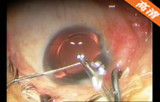

2.2mm微切口白内障超声乳化+人工晶体植入手术

该手术做2.2mm角巩膜缘主切口及侧切口; 前房注入医用透明质酸钠; 连续环形撕囊; 水分离、水分层;超声乳化核和核壳 ,注吸皮质; 抛光前囊和后囊; 前房及囊袋内注入透明质酸钠凝胶; 植入折叠人工晶体; 吸除透明质酸钠凝胶; 水密切口。

关键词: 2.2mm微切口 白内障 超声乳化 折叠人工晶体